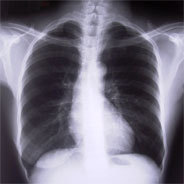

Das Erkennen von Brusttumoren hat tiefgreifende Auswirkungen auf das Leben – und die Art und Weise, wie darüber gesprochen wird. Häufig führen Gefühle wie Befangenheit, Furcht und fehlendes Wissen zu Schweigen.

Doch wie kann man diese Erkrankung anders beschreiben, ohne auf kriegerische Ausdrücke zurückzugreifen – und dabei Möglichkeiten für frische Ansichten und Hoffnungen schaffen? Eine Untersuchung auf der Suche nach Antworten.